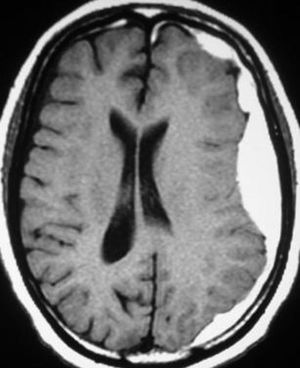

Dx ??

Subdural hematoma

Subdural hematom